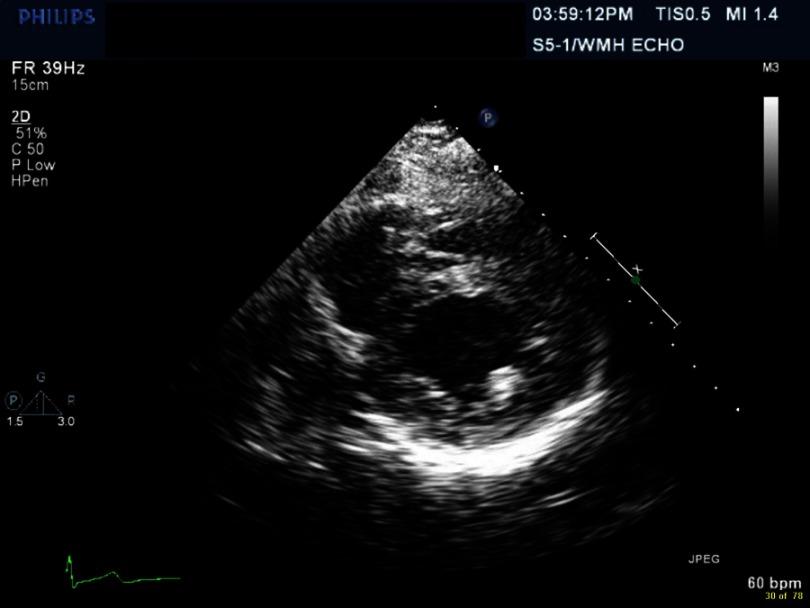

-associated myopericarditis (CAM) has been reported infrequently in the literature. We describe a case of immunocompetent young woman presenting with chest pain, with history of recent travel and diarrhea. Evaluation led to diagnosis of myopericarditis associated with this infection. The patient improved with conservative management. The pathogenesis of CAM remains unknown. Patients present with chest pain, heart failure, pulmonary edema and arrhythmias. Diagnostic evaluation includes EKG, cardiac enzymes, echocardiogram, cardiac MRI and stool culture. Conservative management recommended and routine use of antimicrobial therapy is controversial. CAM is a rare but severe complication of infection. It should be considered as a diagnosis in patients presenting with chest pain with associated gastrointestinal symptoms.